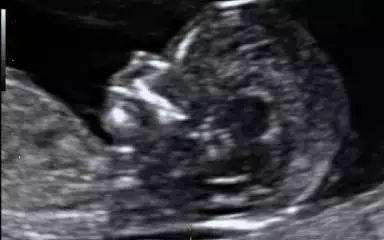

NT检查应该在孕11周~13周+6天时进行,NT检查不宜过晚,因为在孕14周之后,胎儿颈项透明层会随着胎儿淋巴系统的发育完善而消失,致使检查失去意义。

根据孕周或者头臀长(CRL)不同,NT的值是不同的。下面的表给出了不同孕周的NT范围。但是应该说明的是,即便超出了95百分位,也不是意味着宝宝一定不正常,只是风险比较高。此时应该结合超声大排畸的结果,行羊水穿刺。还应该咨询产前诊断医生,给出建议。

做NT检查之前不需要做特殊的准备,正常饮食即可,也不需要憋尿。有时候,医生在做NT检查时发现胎儿位不利于检查,会轻拍孕妇肚子,让胎儿活动一下,这时妈妈们无需过于担忧,保持心情的放松,和医生好好的配合,完成检查,一般经过这些处理,绝大多数宝宝都能逐渐放松,配合医生的检查了。